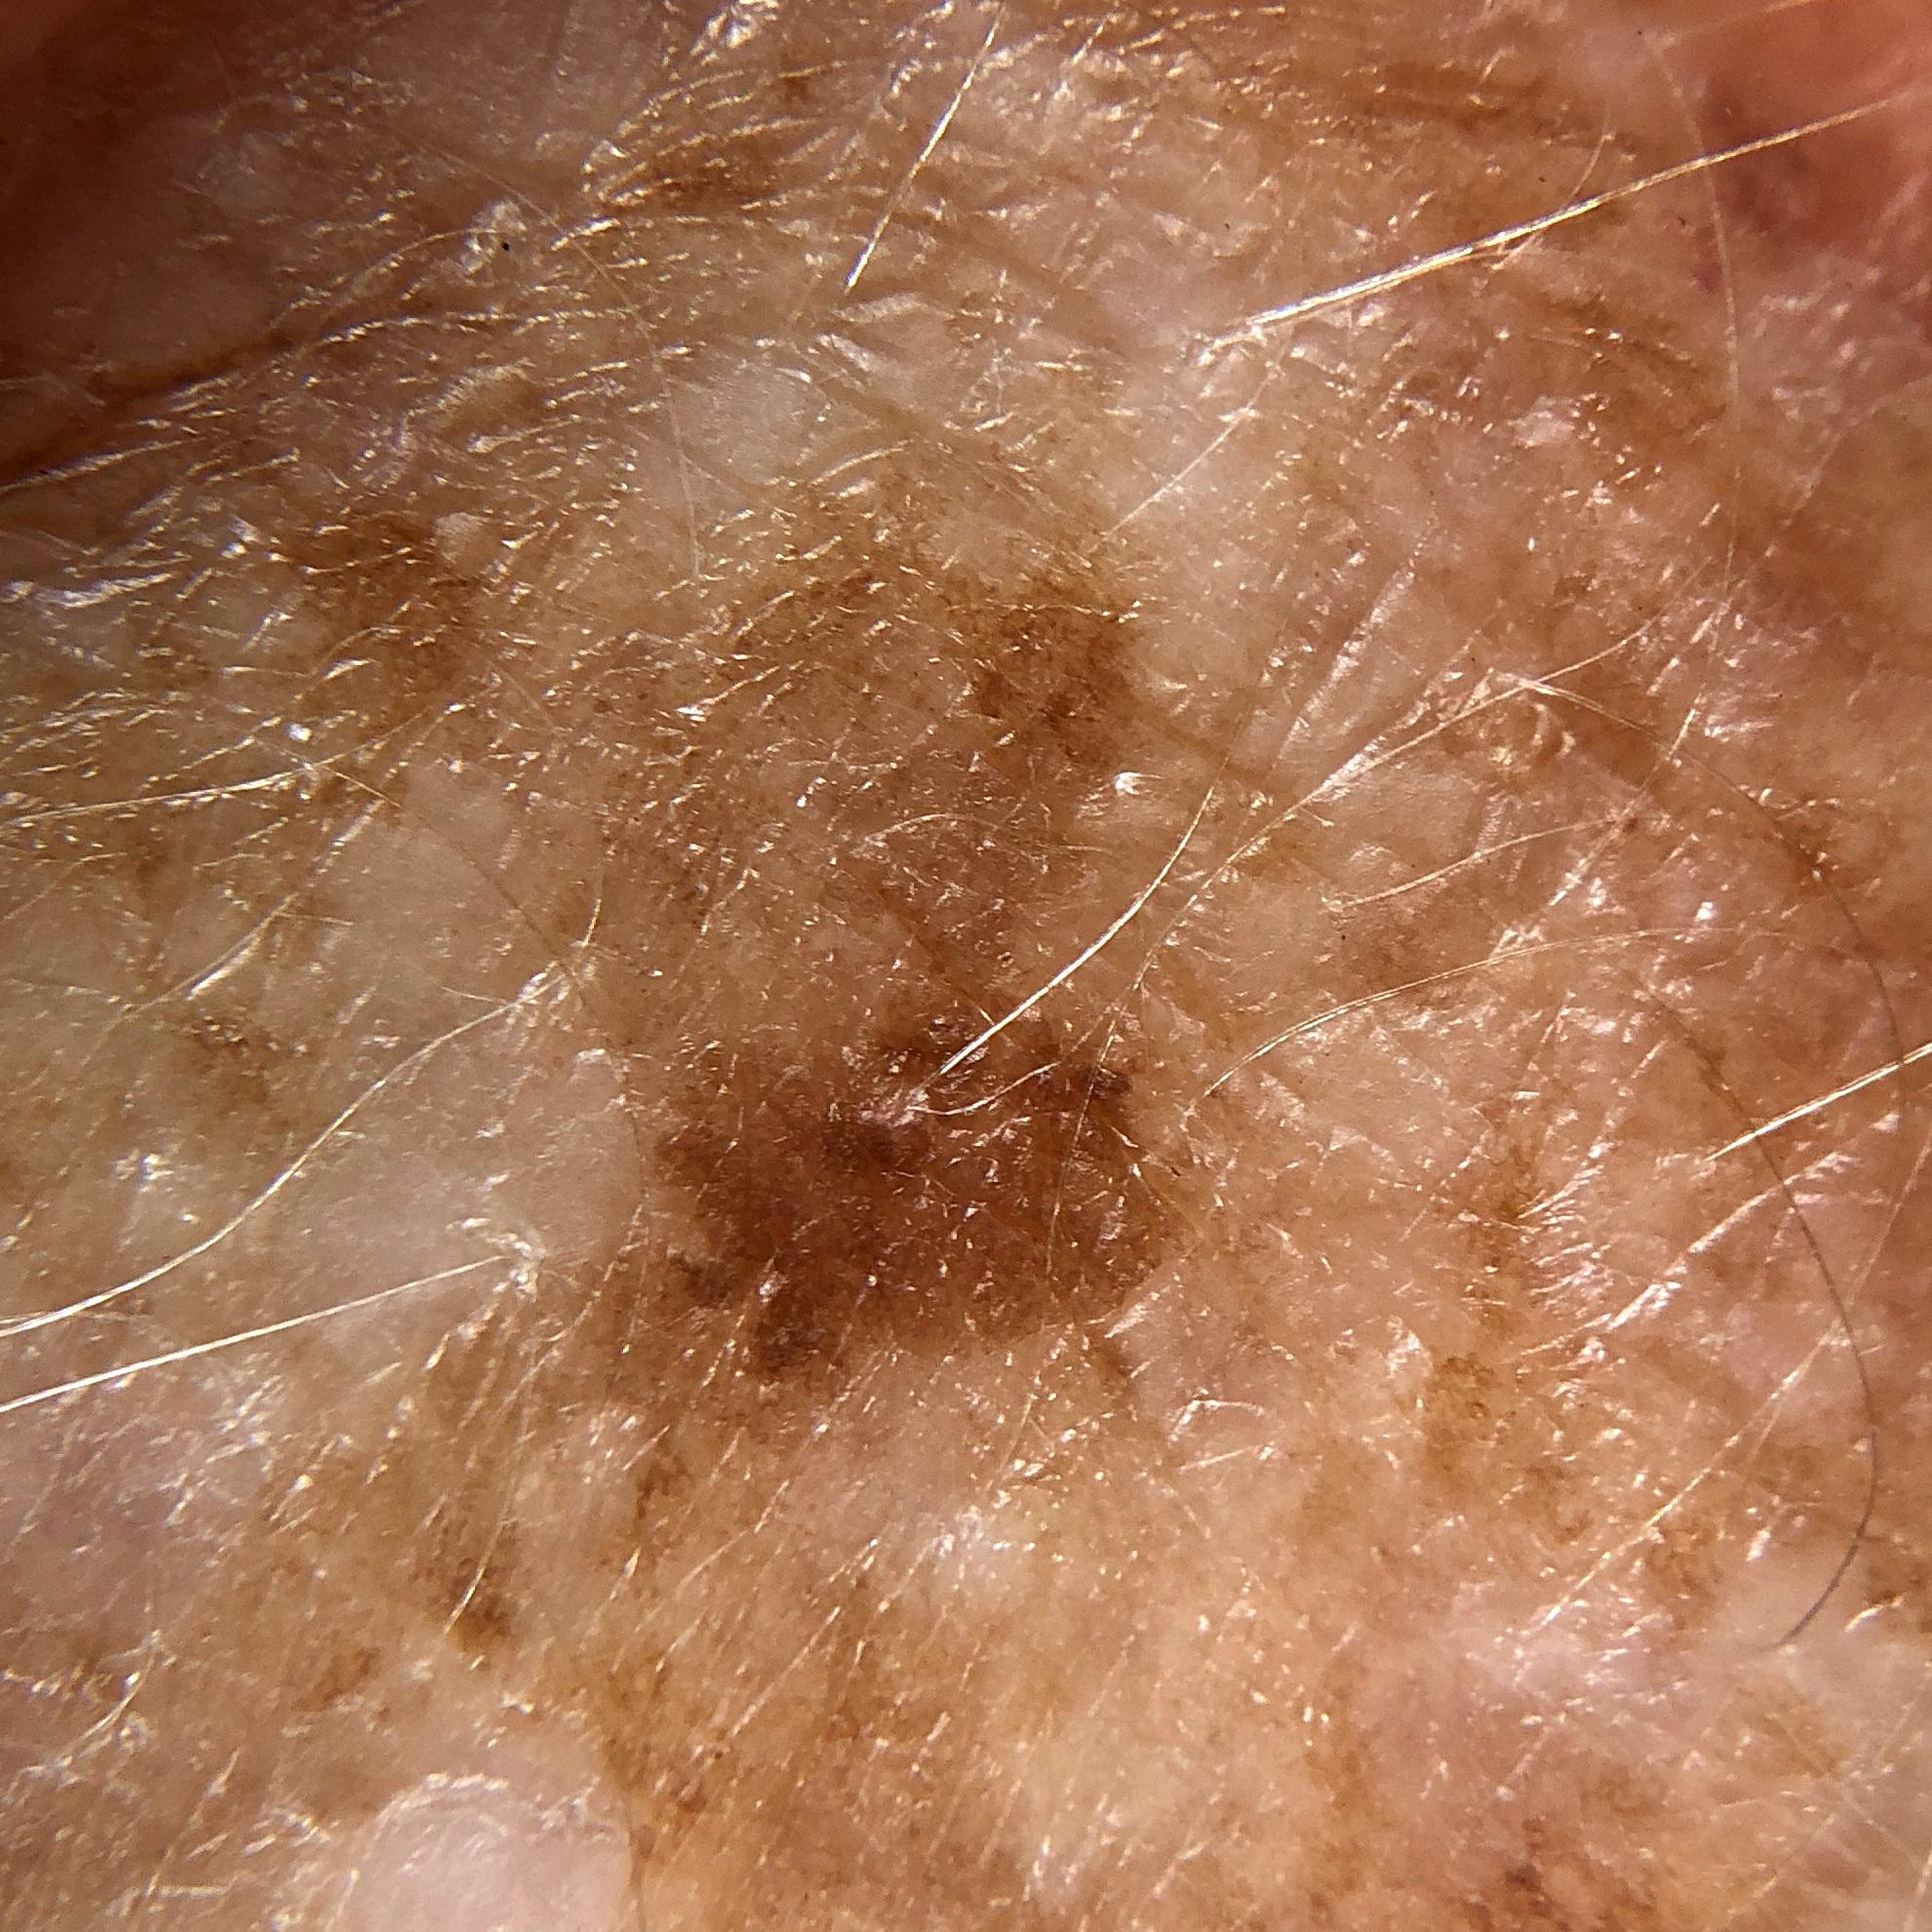

ISIC_1122076

acquisition_day 207

age_approx 65

anatom_site_1 Head and neck

anatom_site_general head/neck

diagnosis_1 Benign

diagnosis_confirm_type single image expert consensus

fitzpatrick_skin_type I

image_type dermoscopic

personal_hx_mm True

sex female